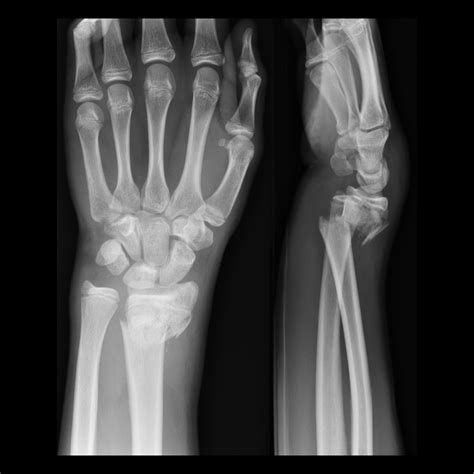

Diagnosis of a Smith Fracture is typically made through:

• Clinical examination, including inspection and palpation of the wrist.

• Radiographic imaging, which may include anteroposterior (AP) and lateral views of the wrist to visualize the fracture and assess the degree of displacement.